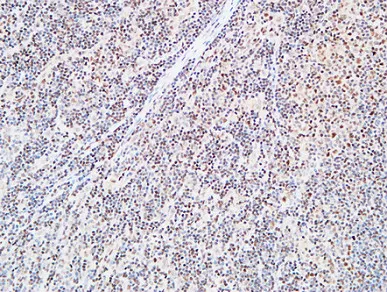

FEN-1 Rabbit Polyclonal Antibody

Cat: APRab10901

Size1:50μl Price1:$118

Size2:100μl Price2:$220

Size3:500μl Price3:$980

Size2:100μl Price2:$220

Size3:500μl Price3:$980